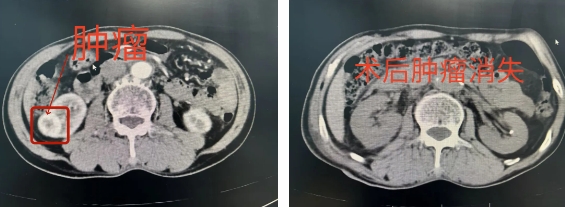

治疗前后

在起搏器的全程护航下,泌尿外科团队凭借丰富经验和娴熟技术,行“腹腔镜下右肾部分切除术”,团队在有限空间内精准操作,快速阻断肾动脉、完整切除肿瘤并完成缝合,核心手术仅耗时30分钟,极大缩短肾脏缺血时间,减少心脏负荷。

患者术后恢复顺利,心脏起搏器顺利撤除,肾功能良好,达到肿瘤根治效果。